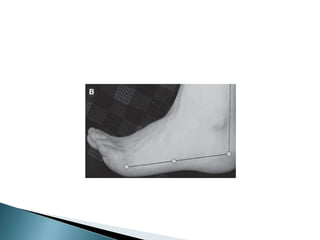

 Ulcera en cara dorsal de los dedos

de los pies

 Cabeza del primer y quinto

metatarsiano

 Base del quinto metatarsiano

 Inserción del tendón de Aquiles

 Prominencias óseas de los bordes

del pie